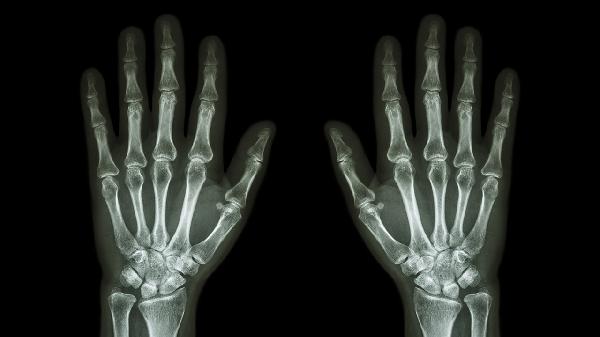

中指关节弯曲咯噔响且疼痛

中指关节弯曲咯噔响且疼痛可能与关节退行性变、腱鞘炎、类风湿关节炎、外伤或痛风性关节炎等因素有关。建议及时就医明确诊断,避免延误治疗。